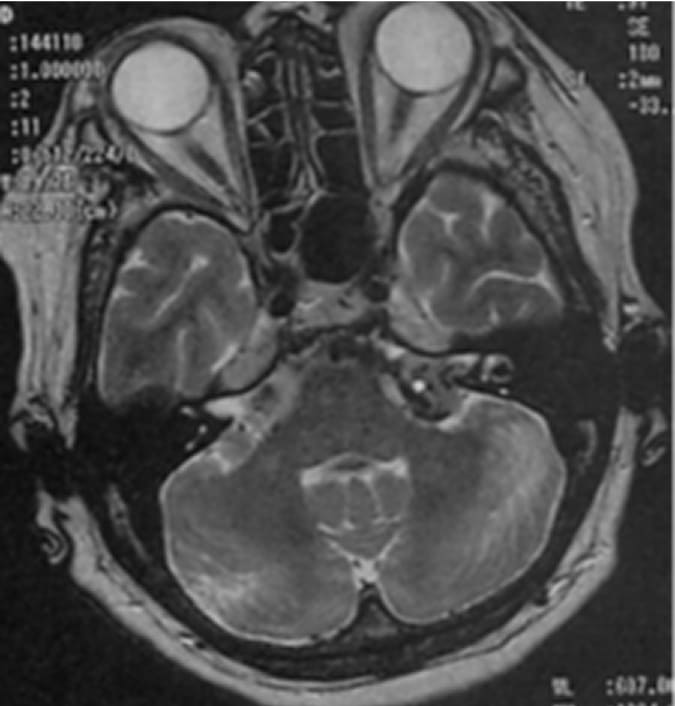

巨大のう胞性聴神経腫瘍症例ガンマナイフ治療後経過

顔面麻痺・聴力障害もなし